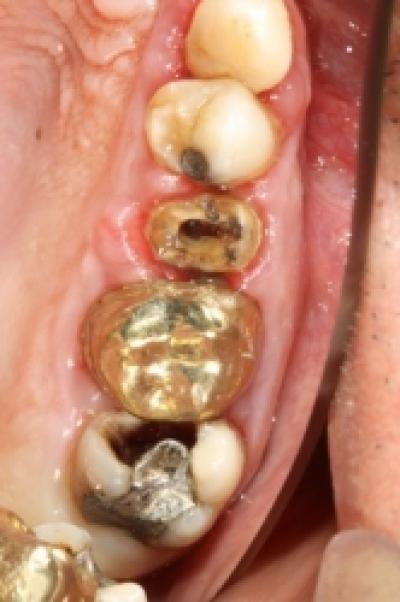

Periodontita reprezinta inflamatia tesuturilor de sustinere a dintilor (parodontiu), mai este cunoscuta ca și boala parodontala (parodontoza).

Periodontita este o leziune ireversibila, care in timp duce la pierderea dintilor de pe arcadele dentare.

Boala parodontala debuteaz... Citeste mai departe